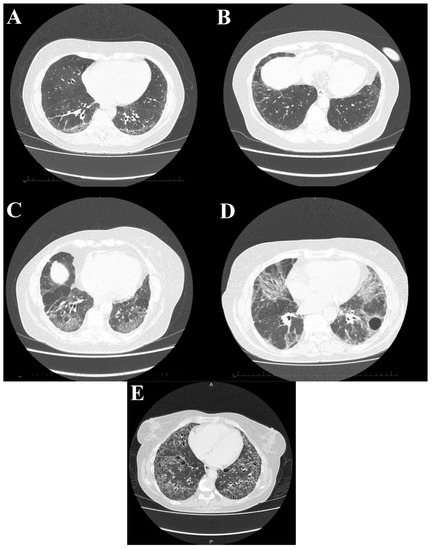

SSc-ILD shows numerous similarities to non-specific interstitial pneumonia (NSIP) both in medical imaging and histopathological examinations [63]. In HRCT (Figure 5) interstitial opacifications are seen in the dorso-basal parts of the lungs—usually of reticular morphology. Ground-glass opacities are also frequent, but typically they spare the subpleural parenchyma [64]. Symptoms that are not as characteristic of SSc but are reported in some of the patients include traction bronchiectasis and honeycombing, although the latter is typical rather in usual interstitial pneumonia than in NSIP [65,66]. The specificity of HRCT exceeds plain radiography, especially in the early stage of pulmonary disease (91% vs 39%) [67]. Abnormalities documented by CT examination correlate with anomalous results of functional tests. Moreover patients that are still asymptomatic in the functional exams might already develop interstitial lesions that might be visualised on a CT scan [6]. Presence of lung disease in HRCT has an impact on the response to treatment and mortality [68].

Figure 5.

High-resolution computed tomography scans show different stages of systemic sclerosis-related interstitial lung disease. (A) Reticular, linear, and minor ground glass opacities; (B) ground glass opacities peripherally in the basal parts of the lower lobes; (C) diffuse ground glass, reticular opacities with discreet interlobular septal thickening in the basal parts of the lower lobes; (D) ground glass opacifications with reticular and linear patterns with traction bronchiectasis with an additional bulla; and (E) interstitial opacifications with extensive honeycombing.